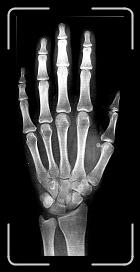

16 7 ANYS 10 MESOS